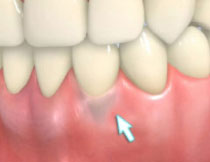

| 歯周病が進行したケースでは盲目下でポケット内の歯石を確実に除去するには限界があります。 | 局所麻酔をした後、歯茎を切開し、明視下にて歯根面の歯石や炎症組織を取り除き、歯周ポケットの除去をおこないました。 |